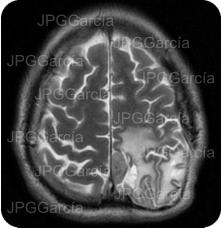

Estudio de IRM de cráneo (T2) como control postquirúrgico en donde se observa edema en la zona quirúrgica